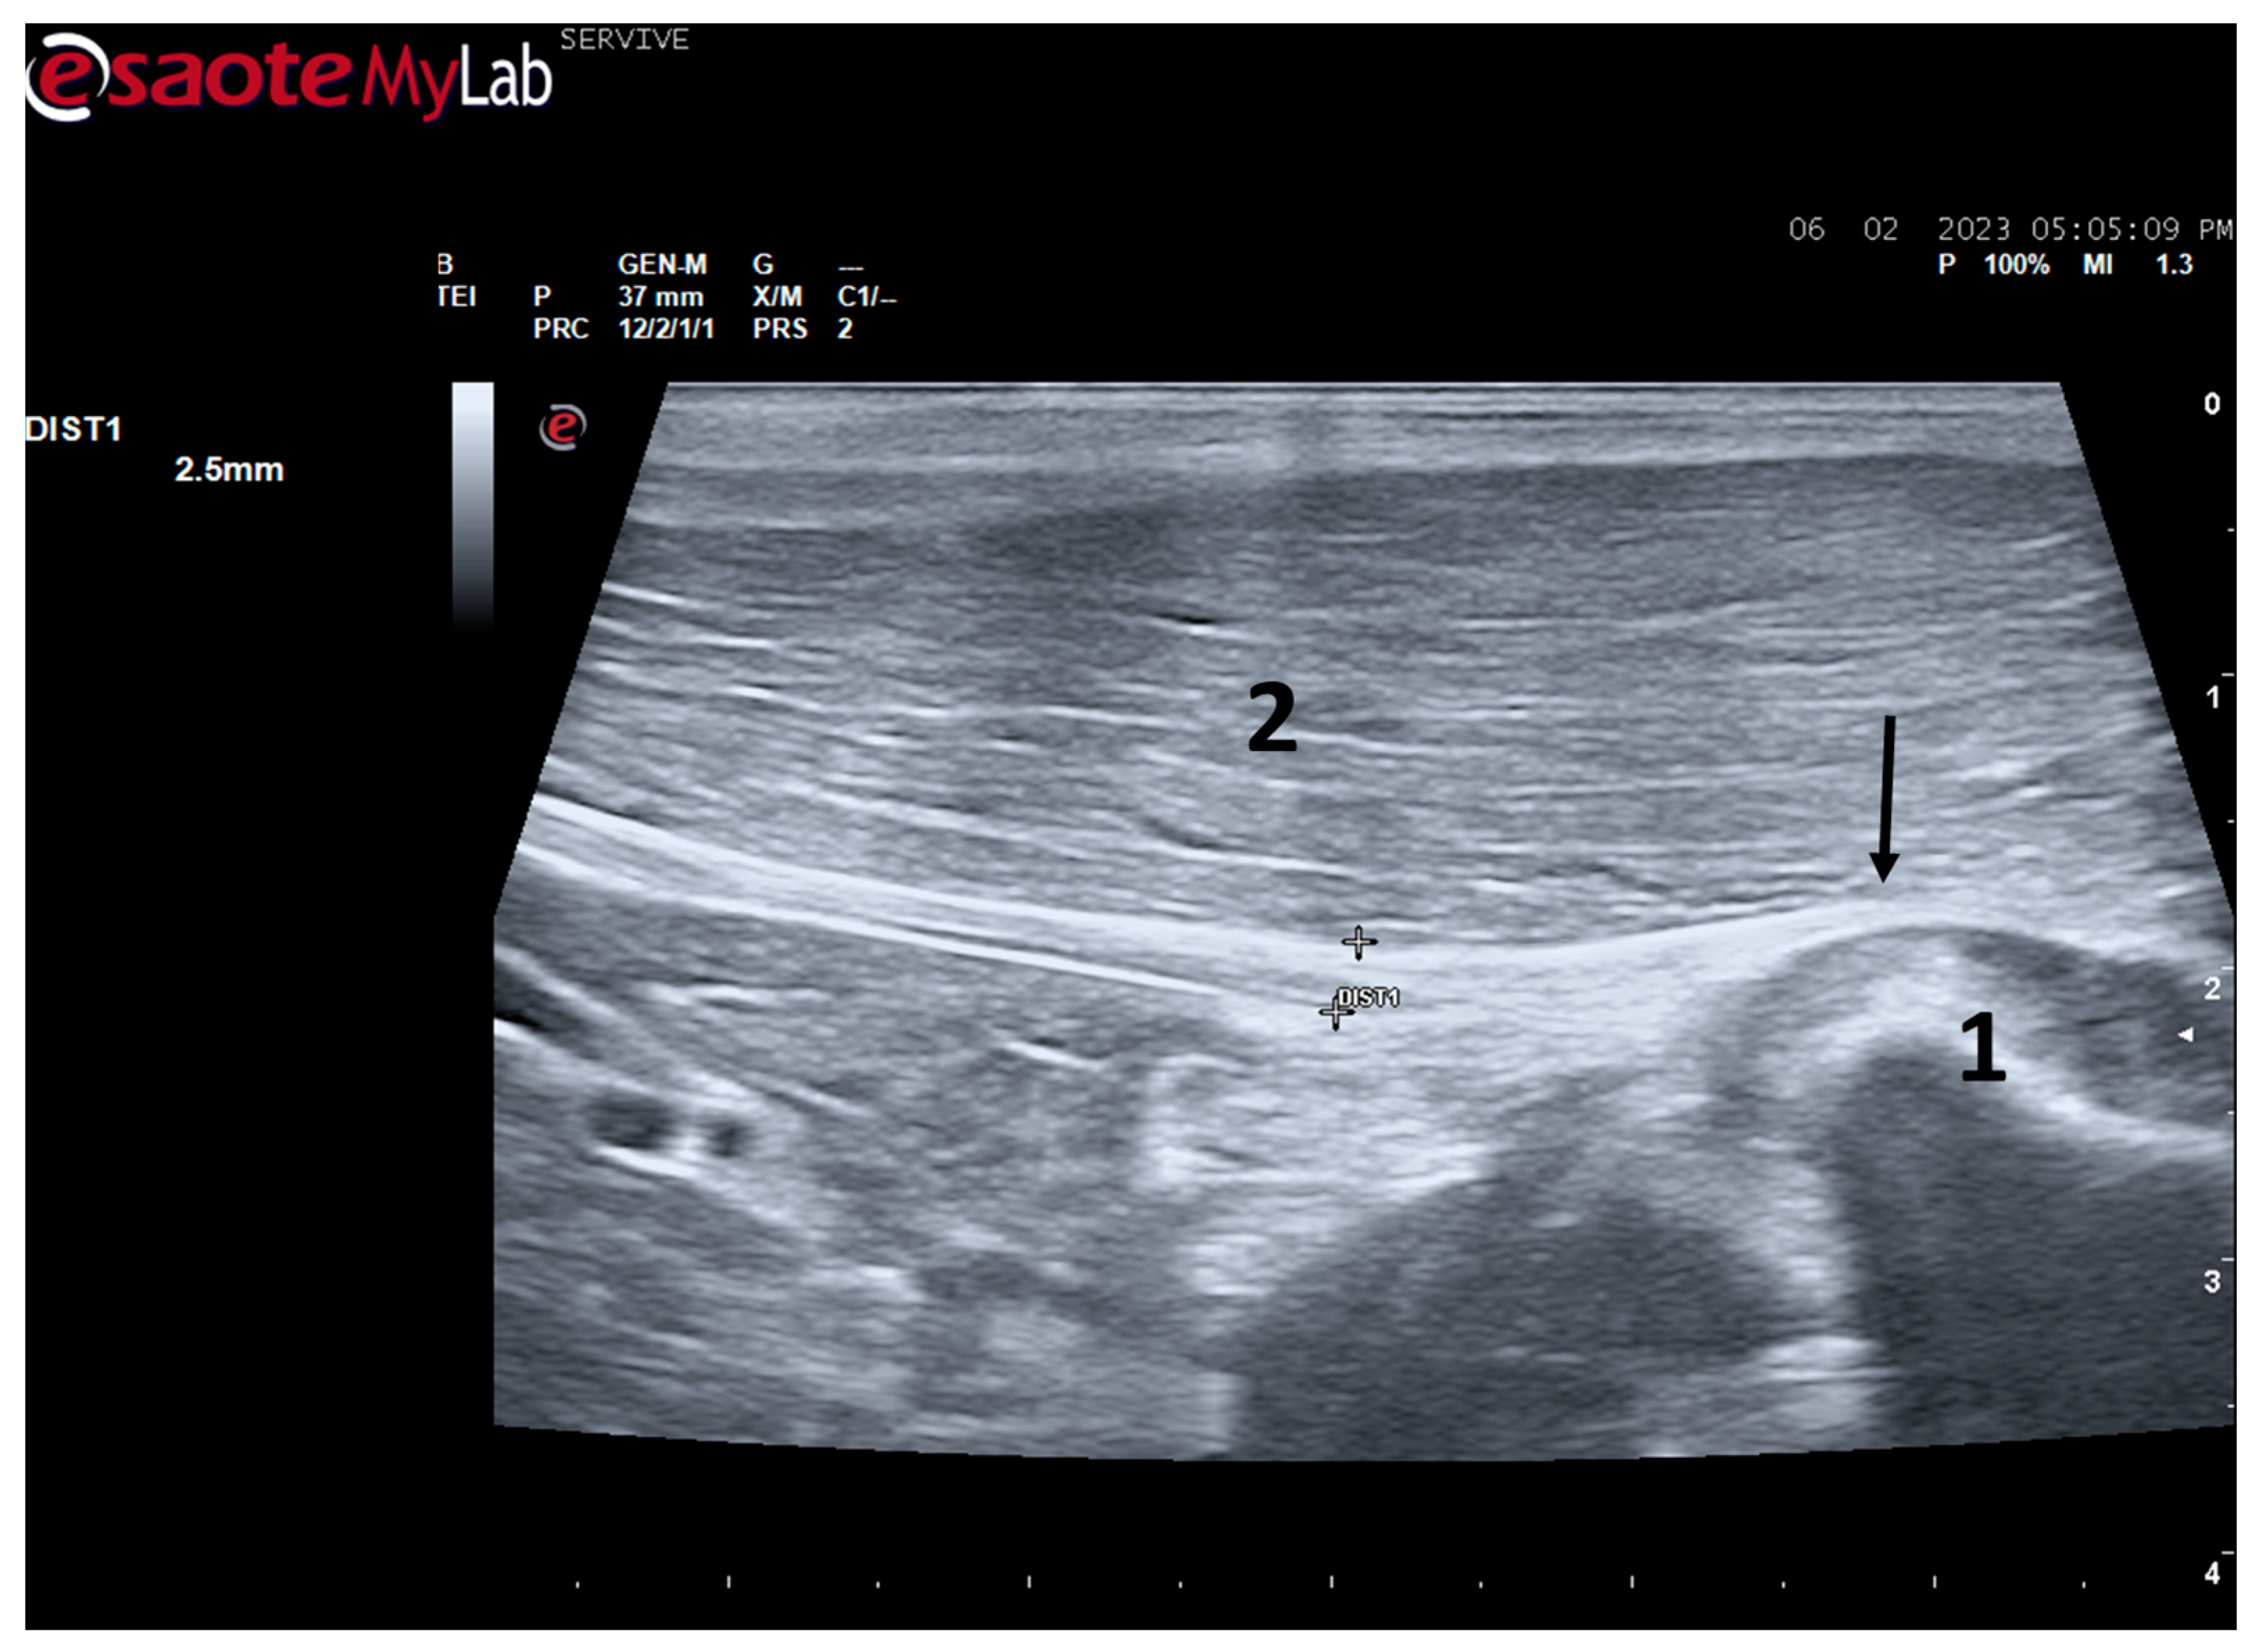

Figure 3.

Ultrasound image of the left sciatic nerve of a sheep after emergence from the greater sciatic foramen: (1) greater trochanter of the femur; (2) biceps femoris muscle; arrow—curvature of the sciatic nerve when passing between the reference bone structures. DIST1 represents the measurement of the diameter of the sciatic nerve.

At the level of the greater ischiatic foramen, the sciatic nerve can be seen advancing between the dorsocaudal aspect of the acetabulum and cranial to the ischial tuberosity, passing over the muscle mass constituted by the gemelli and quadratus femoris muscles, close to the piriformis muscle and advancing caudally to the femur. The presence of these bony structures in the region, although they can be used as anatomical landmarks for nerve identification, can make a more proximal visualization difficult due to the curvature of the sciatic nerve and the hyperechogenicity of the bone that decreases contrast (Figure 3). Accompanying the nerve distally, it is visible between the muscles of the thigh, namely medially to the biceps femoris muscle, laterally to the adductor muscles, and caudally to the femur and the vastus lateralis muscle (Figure 4).

Despite this, ultrasound has some disadvantages, starting with the fact that the nerves to be approached must have a superficial position in order to obtain images and details of greater quality. Nerves in a deeper position or very close to hyperechogenic structures, such as bones, make it difficult to obtain quality images with good contrast (Figure 3) [19]. Although it is a cheaper, less time-consuming, more accessible technique, and ultrasound scanners are more portable and easier to use routinely than the machinery of other techniques such as magnetic resonance imaging, ultrasound allows a lower contrast resolution. However, locally, ultrasound allows a better spatial resolution than resonance applied to the whole body [25]. Microscopically, ultrasonography does not allow an assessment of the anatomy and regenerative phenomena occurring at a subfascicular level, such as axonal and endoneurial growth, requiring the complementary use of stereological techniques.